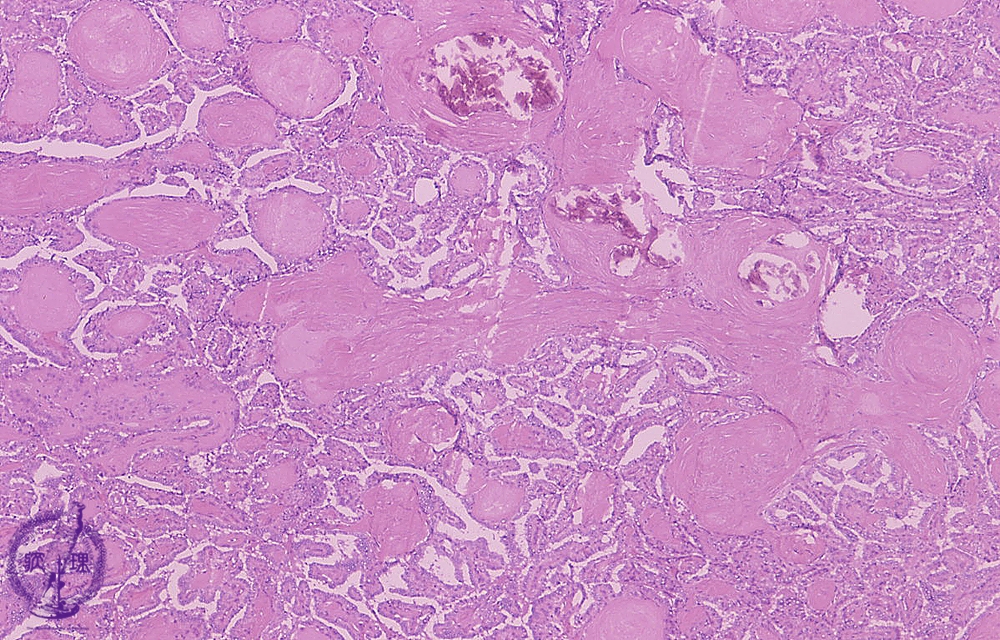

- ★(8)Papillary carcinoma of the thyroid

Microscopic findings (HE stain, low power). Papillary structures of tumor cells and calcification (arrows)